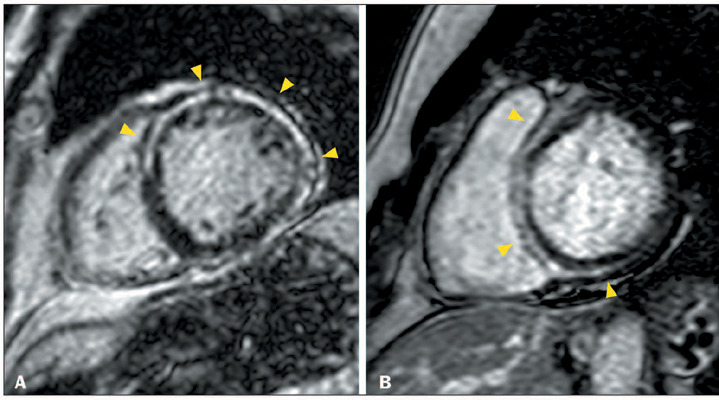

Advances in cardiac magnetic resonance have promoted tissue characterization with high spatial and contrast resolution, and late gadolinium enhancement (LGE) sequences have improved the detection of myocardial fibrosis. The distribution pattern of LGE facilitates differentiation between ischemic and nonischemic etiologies and aids in refining diagnoses within nonischemic cardiomyopathies, suggesting specific etiological factors. A distinctive nonischemic LGE pattern that has recently gained prominence is the ring-like pattern, defined as a subepicardial or mid-wall circumferential or semi-circumferential enhancement, which involves at least three contiguous segments within the same short-axis slice. Initially identified as a diagnostic marker for desmoplakin and filamin C-related cardiomyopathies, the pattern has been reported in nongenetic conditions; nevertheless, it remains an uncommon finding in these diseases. In this article, we aim to present the differential diagnoses of ring-like LGE and its mimics. The combination of epidemiological, clinical, electrocardiographic, and additional features enables a focused refinement of the differential diagnosis associated with ring-like LGE.

Abstract Image